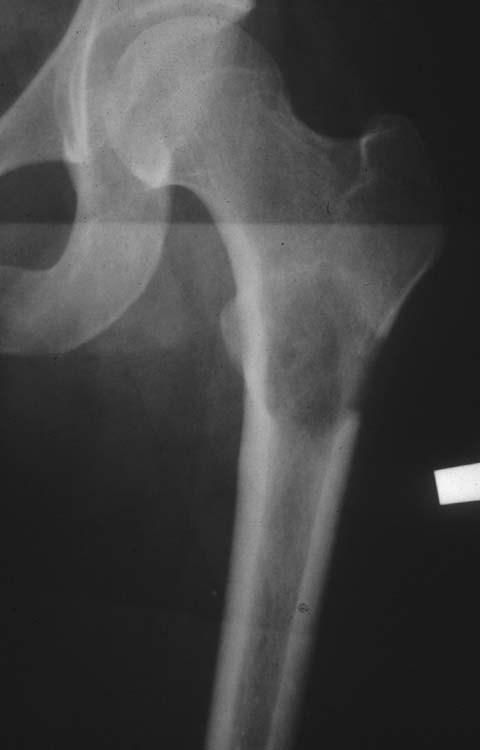

12 yo male comes in with fever, and painful left hip. Below is his XR. Diagnosis? Managment? Treatment?

Ewing Sarcoma